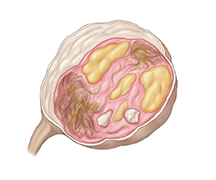

Dermoid cyst

Sometimes cells that are present from birth in the ovary, will start to grow into different kinds of tissue such as skin, fat, hair, and teeth. This kind of cyst is called a dermoid cyst. Dermoid cysts can grow on one or both ovaries. Often they cause no symptoms. But if they leak or the ovary becomes twisted, they can cause severe pain.